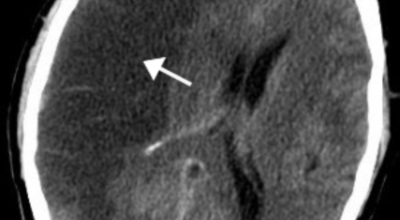

뇌졸중은 뇌경색과 뇌출혈 두가지로 나뉘게 돼요. 먼저 뇌경색은 뇌혈관이 막혀 영양분과 산소를 제공하는 피가 통하지 않는 상태로 원은은 크게 세 가지로 나눌 수 있는데요 동맥경화증이 생겨 좁아진 부위로 인하여 혈액공급이 부족해지거나 좁아지다가 결국 막혀버리는 경우, 큰 혈관에서 분지한 작은 혈관들이 고혈압 등으로 압박을 받으면 혈관이 막히는 경우가 있어요.

또한 심장 판막질환이나 심방세동 또는 심근병 등과 같은 심장 질환이 있는 경우 심장에서 혈전이 만들어지고 그게 뇌로 흘러가게 되면 뇌혈관을 막게 되는 경우가 있어요. 뇌출혈은 뇌경색과 반대로 뇌혈관이 터져서 생기는 뇌내 출혈과 거미막하 출혈로 나누게 돼요. 거미막하출혈은 혈관벽의 약한 부분이 부풀어 오르는 뇌동맥류가 터지는 경우와 관련성이 크다고 해요.